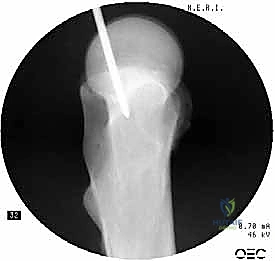

باستخدام جهاز الأشعة السينية المرئية المستمرة (C-Arm Fluoroscopy) داخل غرفة العمليات، يقوم الدكتور هطيف بإعادة العظام المكسورة إلى محاذاتها التشريحية الصحيحة عن طريق الشد والتدوير الخارجي للساق، وكل ذلك يتم مراقبته على الشاشة بدقة متناهية.

من خلال شق جراحي صغير جداً (حوالي 3 إلى 5 سم) أعلى الفخذ (فوق المدور الكبير)، يتم الوصول إلى قمة عظمة الفخذ. يتم إدخال سلك دليلي (Guide Wire) دقيق لتحديد نقطة الدخول المثالية للقناة النخاعية.